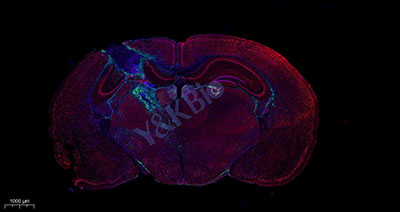

1. 脑组织GFAP/C-FOS双标

8. 镜检拍照:切片于荧光显微镜下观察并采集图像。(DAPI 紫外激发波长330-380nm,发射波长420nm,发蓝光;FITC激发波长465-495nm,发射波长515-555 nm,发绿光;CY3激发波长510-560,发射波长590nm,发红光)。

四、染色结果判读:DAPI染出来的细胞核在紫外的激发下为蓝色,阳性表达为相应荧光素标记的红光和绿光。